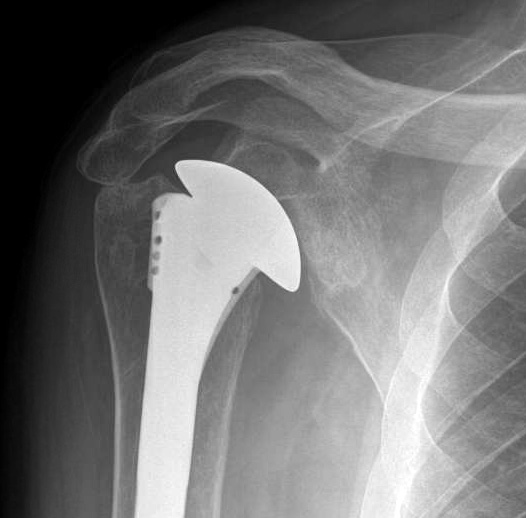

Should non-opeartive management fail, consideration can be given to an arthroplasty. In our hands the safest and most successful is a well balanced hemiarthroplasty.